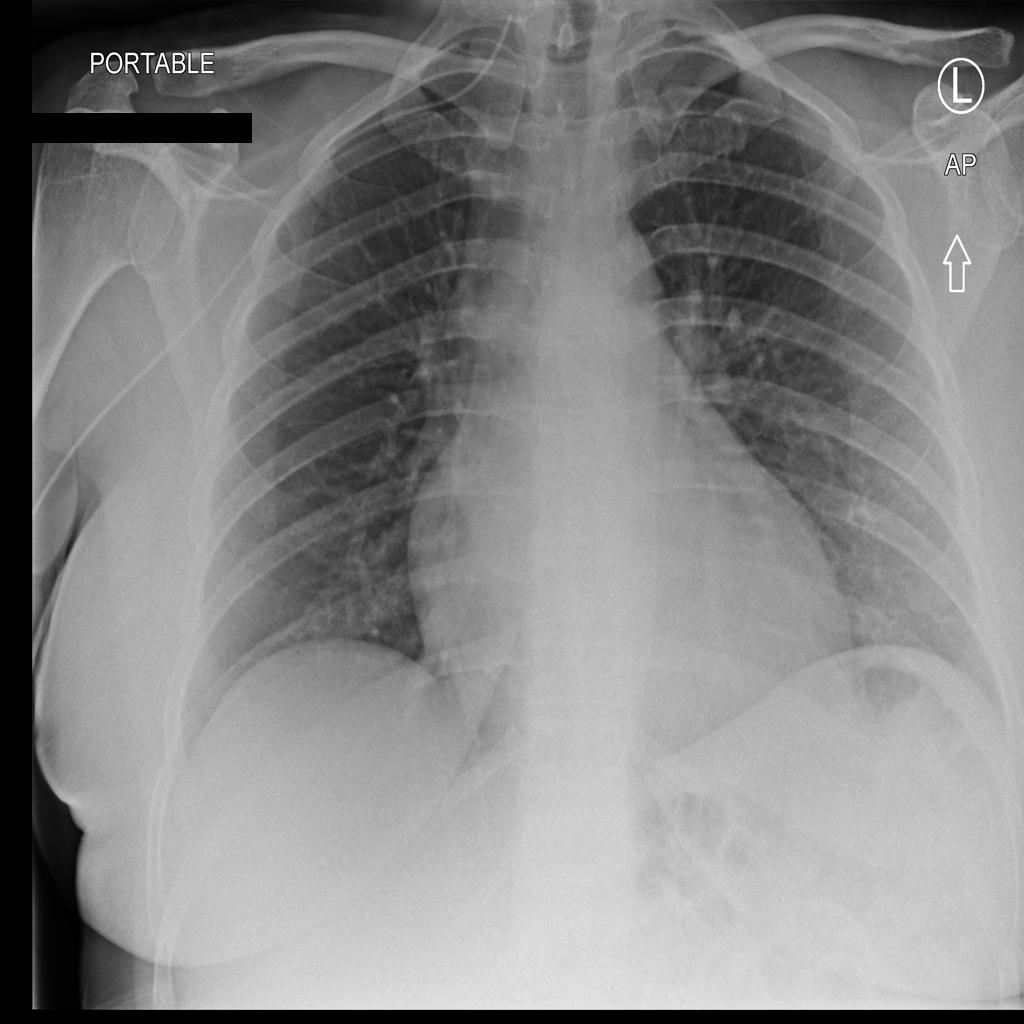

We conclude our analysis with consideration of the ChestXray-14 [RIZ+17] dataset. This dataset contains frontal X-ray images labeled with 14 different conditions. ChestXray-14 is a multi-label tagging task (i.e., a single image can have more than one condition), so we treat each condition as its own binary problem. In this section, we focus on the condition Effusion. Results on other conditions can be found in Appendix C.3.

The trained SVM identifies visually distinguishable failure mode directions in latent space. As shown in Figure 11, the representative images flagged by this SVM as most incorrect are blurrier and less bright. Moreover, this trend is not reflected by the least confident images, indicating that our framework is isolating a different trend than the one corresponding to ordering the images by base model confidence.

In fact, we find that the SVM may be picking up on the position in which the exam was conducted. While the majority of the X-rays are Posterior-Anterior (PA) radiographs, a little over a third are Anterior-Posterior (AP). PA radiographs are usually clearer, but require the patient to be well enough to stand [TB20]. Examples of AP and PA radiographs from the dataset can be found in Appendix C.3.

As shown in Table 13, the SVM for the class “no effusion” flags a large number of the AP radiographs as incorrect. This indicates that the model might indeed rely on the position in which the radiograph was taken to predict whether the patient was healthy. Moreover, the SVM selects the AP examples more consistently than ordering the radiographs by the base model’s confidence (Figure 13).